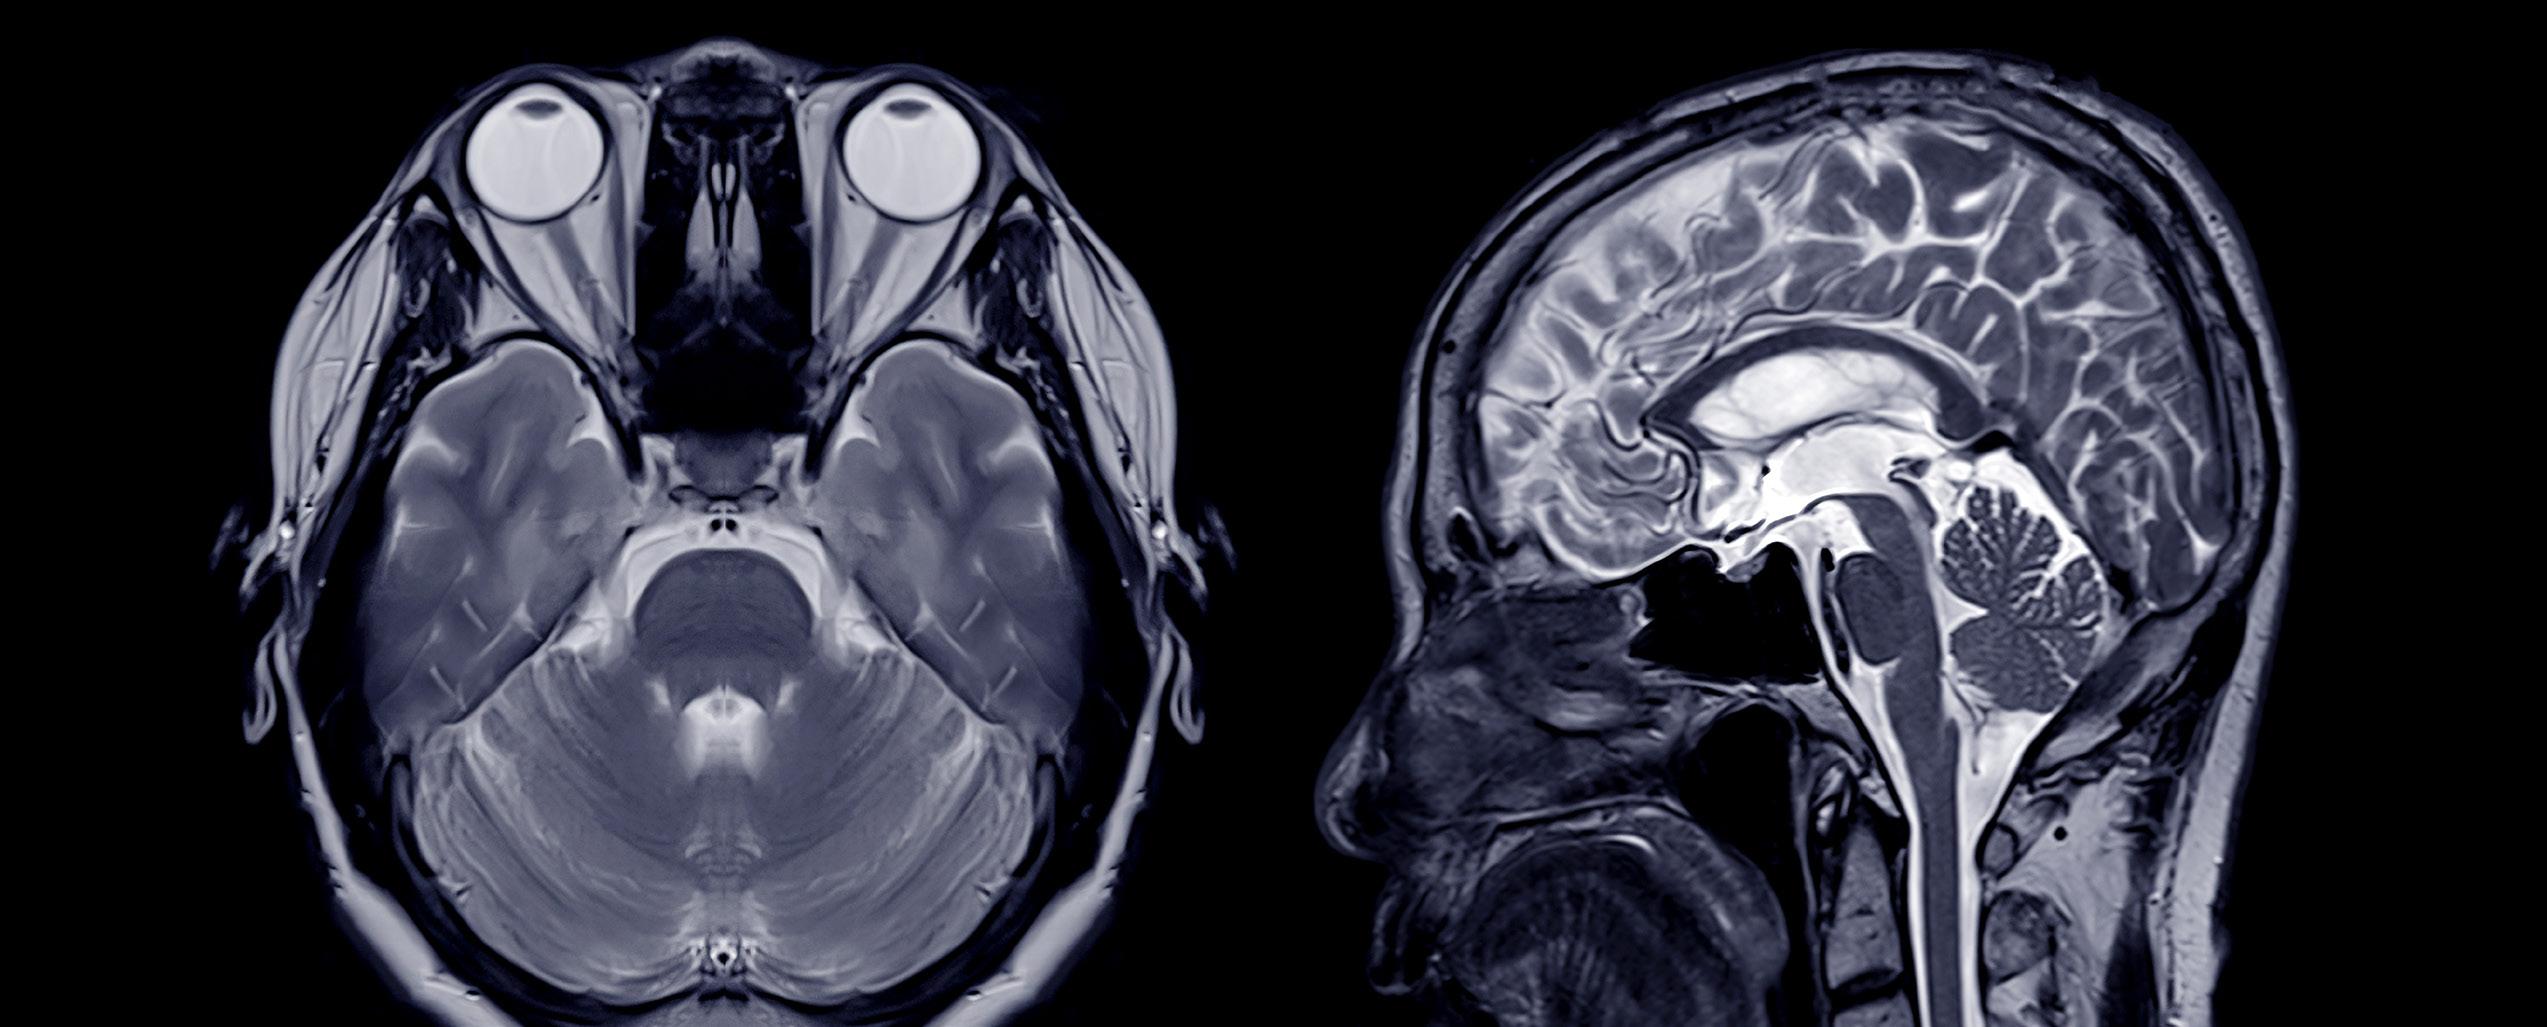

For Benjamin Tinsley, diagnostic imaging support, advanced field service engineer II at Baylor Scott & White Health in Dallas, Texas, the introduction to HTM came out of the realization for the need for biomeds.

“My journey into the HTM field started while I was working with a nonprofit organization in Nicaragua, where I helped coordinate mobile medical clinics. During that time, I noticed that a lot of the equipment we relied on was constantly breaking down – and there was rarely anyone around who could fix it properly. It got me thinking someone out there has to be responsible for keeping this equipment running. That sparked my interest in the technical side of healthcare,” Tinsley says.

After graduation, Tinsley began his career with Siemens Healthineers as an imaging field service engineer.

“I’ve focused my experience on keeping this equipment running smoothly. It’s rewarding to know that my work helps support accurate diagnoses and effective treatments,” he says.

“One of the main challenges I’ve faced in my current role as an advanced engineer is maintaining a consistent preventive maintenance schedule in the cath labs. These labs are high-demand environments where patient care is always the top priority, so finding the right windows of time to perform thorough maintenance without disrupting critical procedures can be quite challenging,” Tinsley says.

He says that in addition to these challenges, he has been involved in projects focused on upgrading and optimizing the imaging systems within the cath, IR, OR, and EP labs.

“These projects have included system updates, integration of new technologies, and workflow improvements aimed at improving operational reliability and supporting the clinical teams in delivering quality care,” Tinsley says.

When somebody enjoys their vocation, it means that they likely do excellent work. Diagnostic imaging is made that much more precise thanks to this HTM professional.